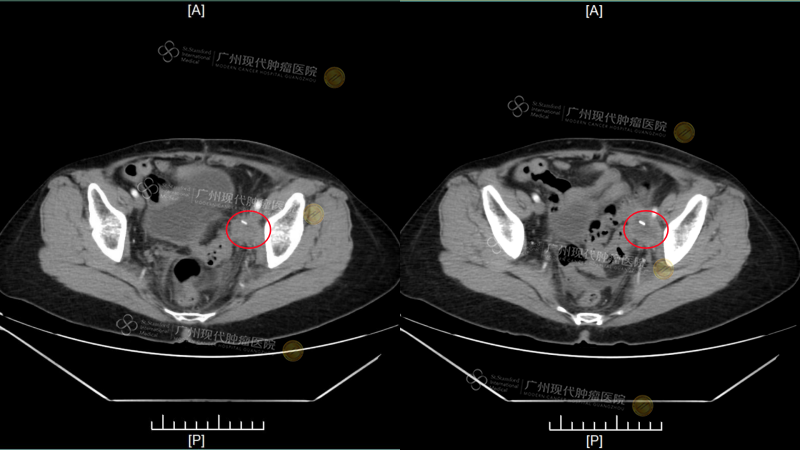

After refusing further treatment, FOO AI KIM seemed to have given up all hope, wanting only to enjoy whatever life she had left. In August 2025, the tumor and the pain returned with a vengeance—a pelvic lymph node recurrence had enlarged to approximately 3.9*3.3 cm, compressing the leg nerve and causing severe swelling in her left leg. A new metastatic tumor, about 0.9*1.6 cm, also appeared in her liver. “At that time, I could only rely on high doses of painkillers to get me through each day's sleep,” she shared. With pain and helplessness as her constant companions, she couldn’t help but plead in her prayers: “Is this really all that’s left for the rest of my life?”

(This CT scan showed results of her admission examination at our hospital on September 22)

(Pelvis: Tumor reduced by 80% after two treatments) (The white highlights indicate the implanted particles)